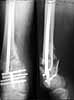

A mail 27 y.o. was operated Apr 2, 2002 2 weeks after injury (impact by a heavy construction) - he had open Gustilo II distal femoral fracture (image 1). Antegrade closed nailing by UFN 11 mm was performed (image 2). The second leg was amputated above the knee at the initial hosptial. To provide early weight bearing 6 mm locking screws were used so sll static holes were drilled accordingly. 2 months after the surgery he started to load the limb, before only knee ROM excersises were perfomed. The cyclic loadings produces stress riser and the nail was broken 10 days ago (image 3). Now he admitted to us again. It is the first case of such complication we meet. Now i plan to push the broken fragment distally and then perfrom retrograde nailing by UFN (distal femoral nails are not available in my settings). If the attempt would be too complicated we'll change to XF. Or plating is a good option here?

THX for the valuable suggestions about the subject. Actually we don't have a set for broken implant retrieval through the antegrade incision. So as we planned the piece was pushed out distally and the nail was replaced by the same but inserted from below. I locked it statically at the moment. Comments are welcome.